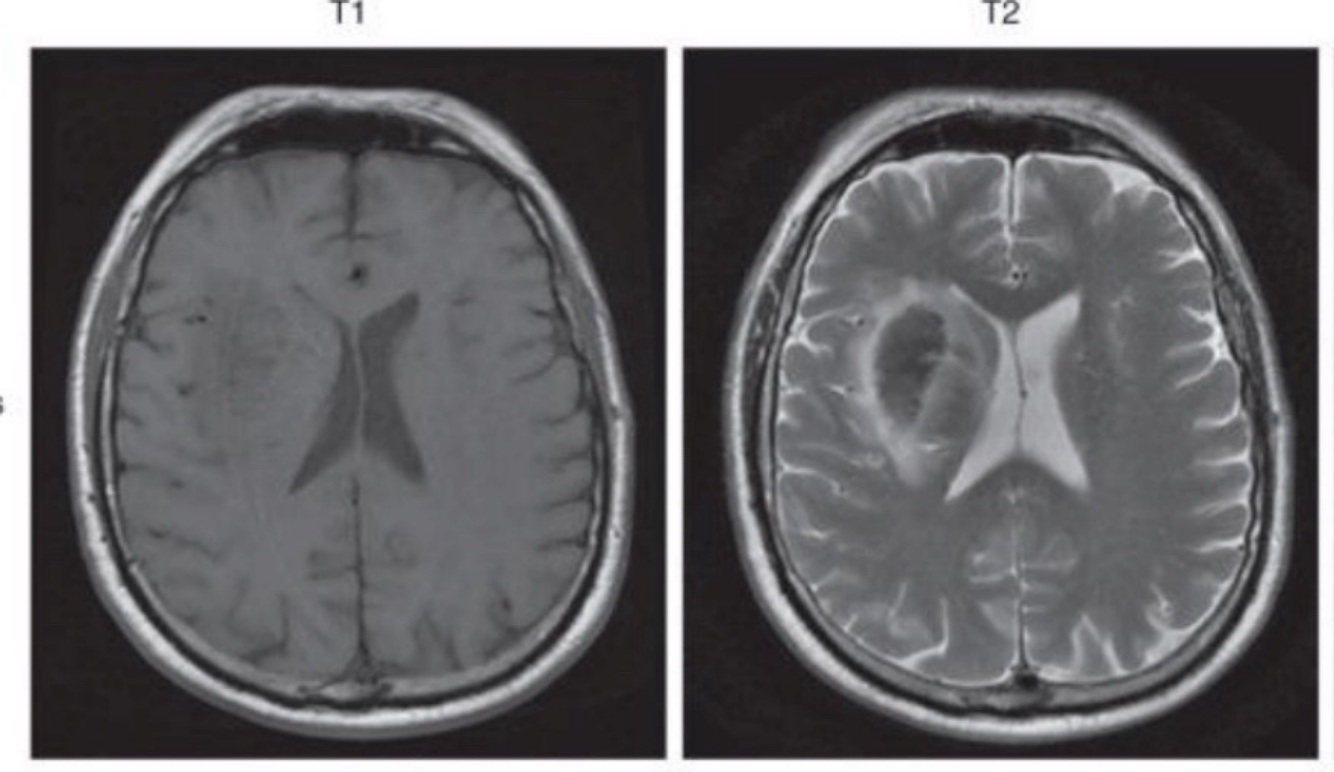

Q

A

EVC isquémico crónico